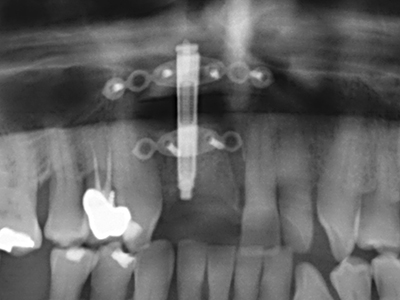

Indikation: Sinuslift

Die Präparation des lateralen Fensters bei der externen Sinusbodenelevation stellt gerade für chirurgisch unerfahrene Implantologen eine große Herausforderung dar. Die knöcherne Bedeckung der Kieferhöhle ohne eine Verletzung der darunterliegenden Schneider’schen Membran abzutragen ist dabei nur ein Teil der Operation – nach Schaffung eines ausreichenden Zugangs muss die Kieferhöhlenschleimhaut vorsichtig mobilisiert werden, um Raum für das einzubringende Material bzw. die Implantate zu schaffen. In dieser Indikation ist die Piezochirurgie zweierlei hilfreich: zum einen kann durch Verwendung diamantierter Instrumente eine selektive Knochenabtragung erfolgen und die darunter liegende Schleimhaut bleibt bei vorsichtiger Vorgehensweise intakt. Zum anderen unterstützen die Ultraschallfrequenzen zusätzlich eine komplikationslose Ablösung der Schleimhaut – sie werden durch spezielle stumpfe Ansätze in den Spaltraum zwischen Schleimhaut und Kieferhöhlenboden übertragen (Cassetta, Ricci et al. 2012, Pereira, Gealh et al. 2014) (Rickert, Vissink et al. 2013). So erscheint es nicht verwunderlich, dass in aktuellen Übersichtsarbeiten über die externe Sinusbodenelevation neben der Verwendung von rauen Implantatoberflächen und dem Einsatz von Knochenersatzmaterialien auch der Einsatz von piezoelektronischen Geräten als positiv bewertet wird (Wallace, Tarnow et al. 2012).